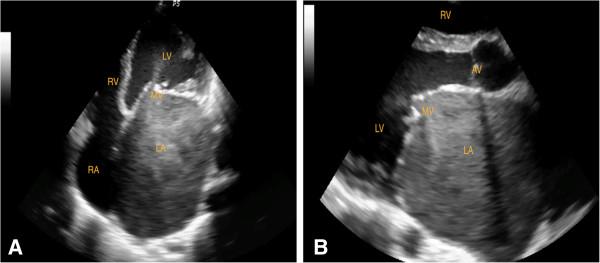

Mitral stenosis, one of the grave consequences of rheumatic heart disease, was generally considered to take decades to evolve. However, several studies from the developing countries have shown that mitral stenosis follows a different course from that seen in the developed countries. This study reports the prevalence, severity and common complications of mitral stenosis in the first and early second decades of life among children referred to a tertiary center for intervention.

Medical records of 365 patients aged less than 16 and diagnosed with rheumatic heart disease were reviewed. Mitral stenosis was graded as severe (mitral valve area < 1.0 cm2), moderate (mitral valve area 1.0-1.5 cm2) and mild (mitral valve area > 1.5 cm2).

Mean age at diagnosis was 10.1 ± 2.5 (range 3-15) years. Of the 365 patients, 126 (34.5%) were found to have mitral stenosis by echocardiographic criteria. Among children between 6-10 years, the prevalence of mitral stenosis was 26.5%. Mean mitral valve area (n = 126) was 1.1 ± 0.5 cm2 (range 0.4-2.0 cm2). Pure mitral stenosis was present in 35 children. Overall, multi-valvular involvement was present in 330 (90.4%). NYHA functional class was II in 76% and class III or IV in 22%. Only 25% of patients remember having symptoms of acute rheumatic fever. Complications at the time of referral include 16 cases of atrial fibrillation, 8 cases of spontaneous echo contrast in the left atrium, 2 cases of left atrial thrombus, 4 cases of thrombo-embolic events, 2 cases of septic emboli and 3 cases of airway compression by a giant left atrium.